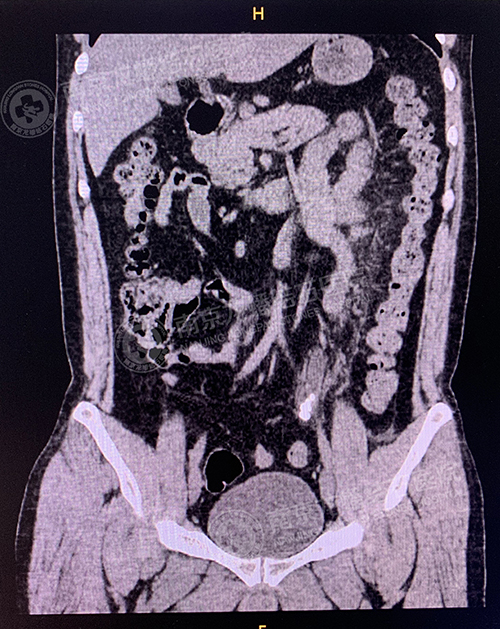

术前

术后

2020年5月9日12时35分,泌尿外科二病区主任梁和建成功为呼先生实施了经尿道左输尿管镜钬激光碎取石术,成功将左输尿管下段数枚不规则黄褐色结石击碎取出。最大约1.3cm。